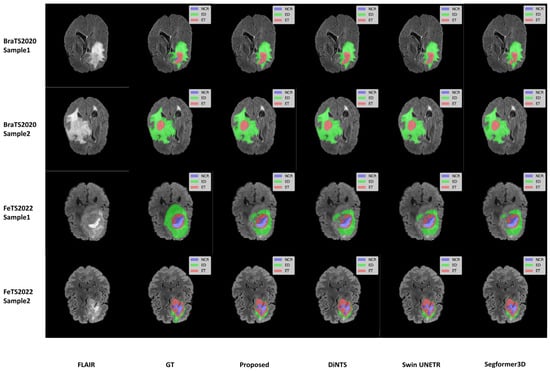

We selected two samples from each dataset of BraTS2020 and FeTS2022 for qualitative analysis using the methods proposed in this paper, specifically DiNTS, Swin UNETR, and Segformer3D. The results of the visualization are presented in Figure 5. To facilitate presentation, the 3D medical images will be displayed using a grayscale map of intermediate 2D slices along the depth dimension, with different tumor subregions distinguished by varying colors. Each tumor part is represented by a corresponding color. We chose the Flair sequence image as the primary reference point, while the Ground Truth (GT) indicates the segmented region of the label mask.

Figure 5. Qualitative visualization of brain tumor segmentation results on selected axial slices from the BraTS2020 and FeTS2022 datasets. For each sample, the FLAIR MRI sequence is shown first, followed by the Ground Truth (GT) segmentation and predictions from our proposed WIAF model, DiNTS, Swin UNETR, and Segformer3D. In the segmentation masks, tumor subregions are color-coded as follows: enhancing tumor (ET) in red, peritumoral edema (ED) in green, and necrotic and non-enhancing tumor core (NCR/NET) in blue.